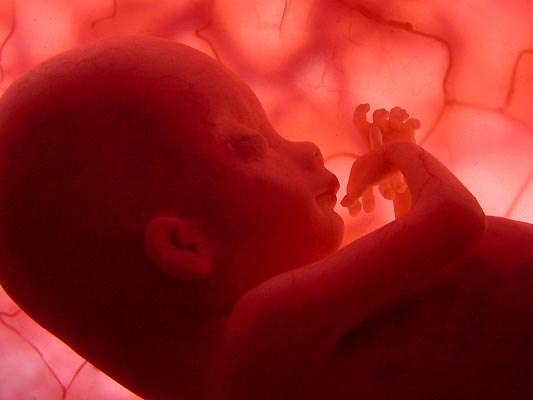

Paso a paso. El feto flota suavemente en el interior del vientre materno.